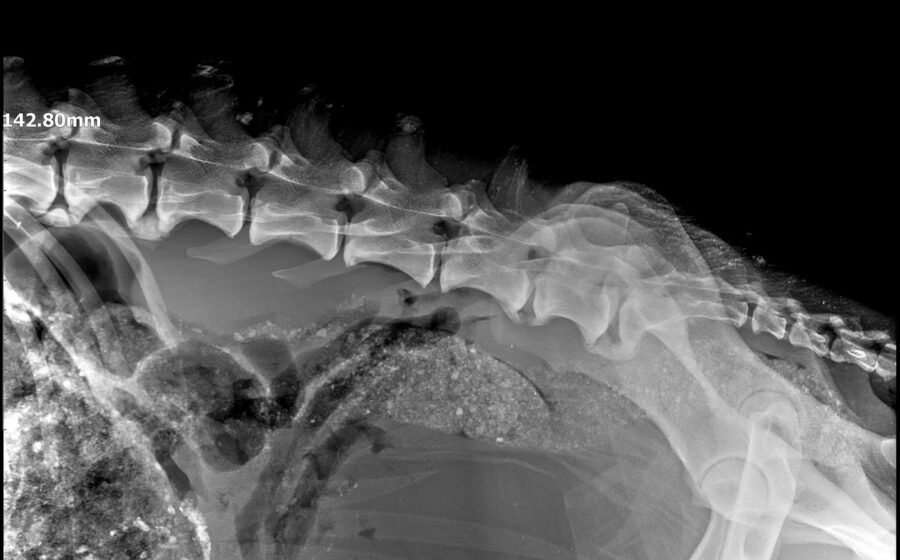

Völlig heruntergekommen, bis auf die Haut abgemagert und nicht mehr in der Lage zu laufen wurde Robinson unter einer Brücke gefunden. Hier hat er wohl schon längere Zeit hilflos gelegen. Robinson wurde in ein privates Shelter in Baia Mare gebracht und tierärztlich untersucht. Neben seinem katastrophalen Allgemeinzustand wurde eine Fehlstellung der Hinterbeine aufgrund von Mangelernährung festgestellt. Diese Fehlstellung scheint auch für seine Unfähigkeit zu laufen verantwortlich zu sein. Eventuell ist der arme Kerl auch inkontinent.